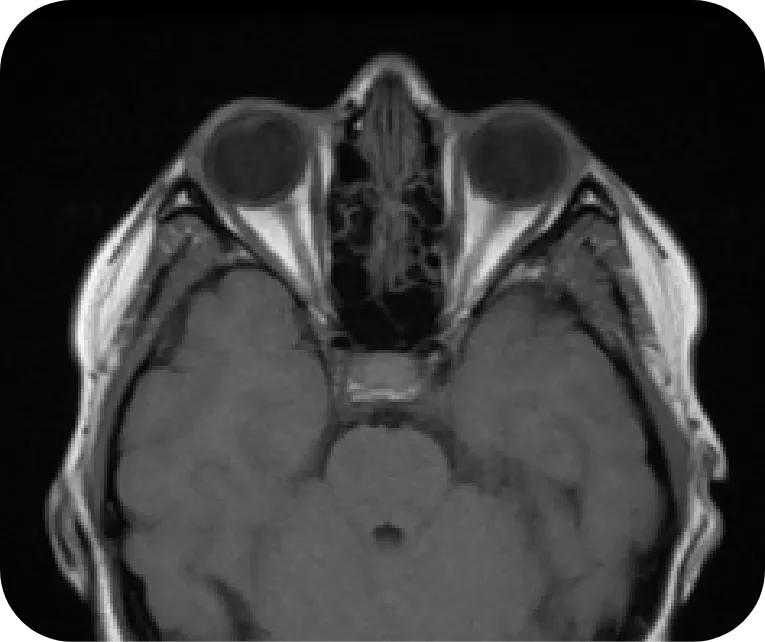

Optic Nerve

Normal

Axial T1-weighted image showing normal optic nerve

Courtesy of Associate Professor Frank Gaillard, Radiopaedia.org, rID:37605.